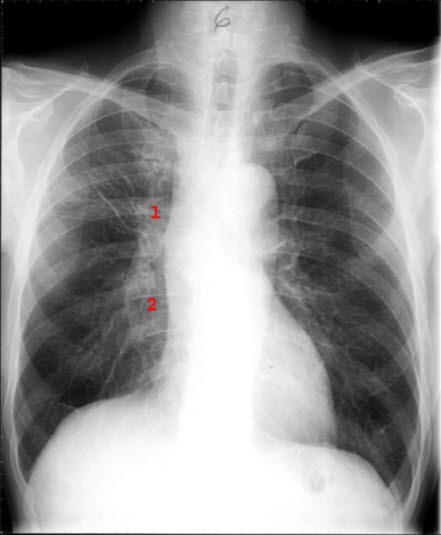

Småcellet anaplastisk carcinom

Etter cytostatikabehandling

Markerte kjertler i hilus på h. side (1 og 2). Atelektasen er borte, bare noe stripeforma arrvev i overlappen på høyre side

Normalt lungevev på v. side